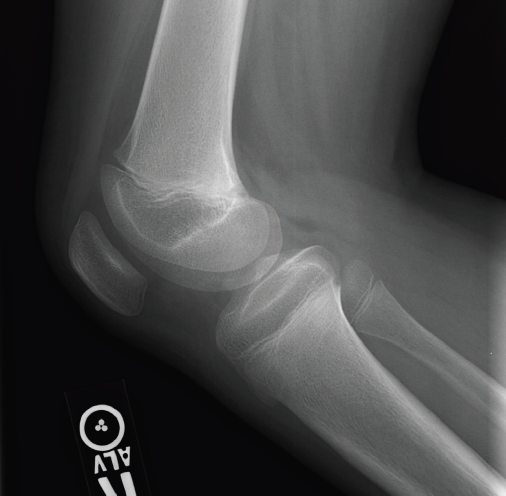

Radiographs obtained in the ED (Figures 1, 2, and 3) helped guide management and diagnosis.

Figure 2. Lateral radiograph of the right knee.